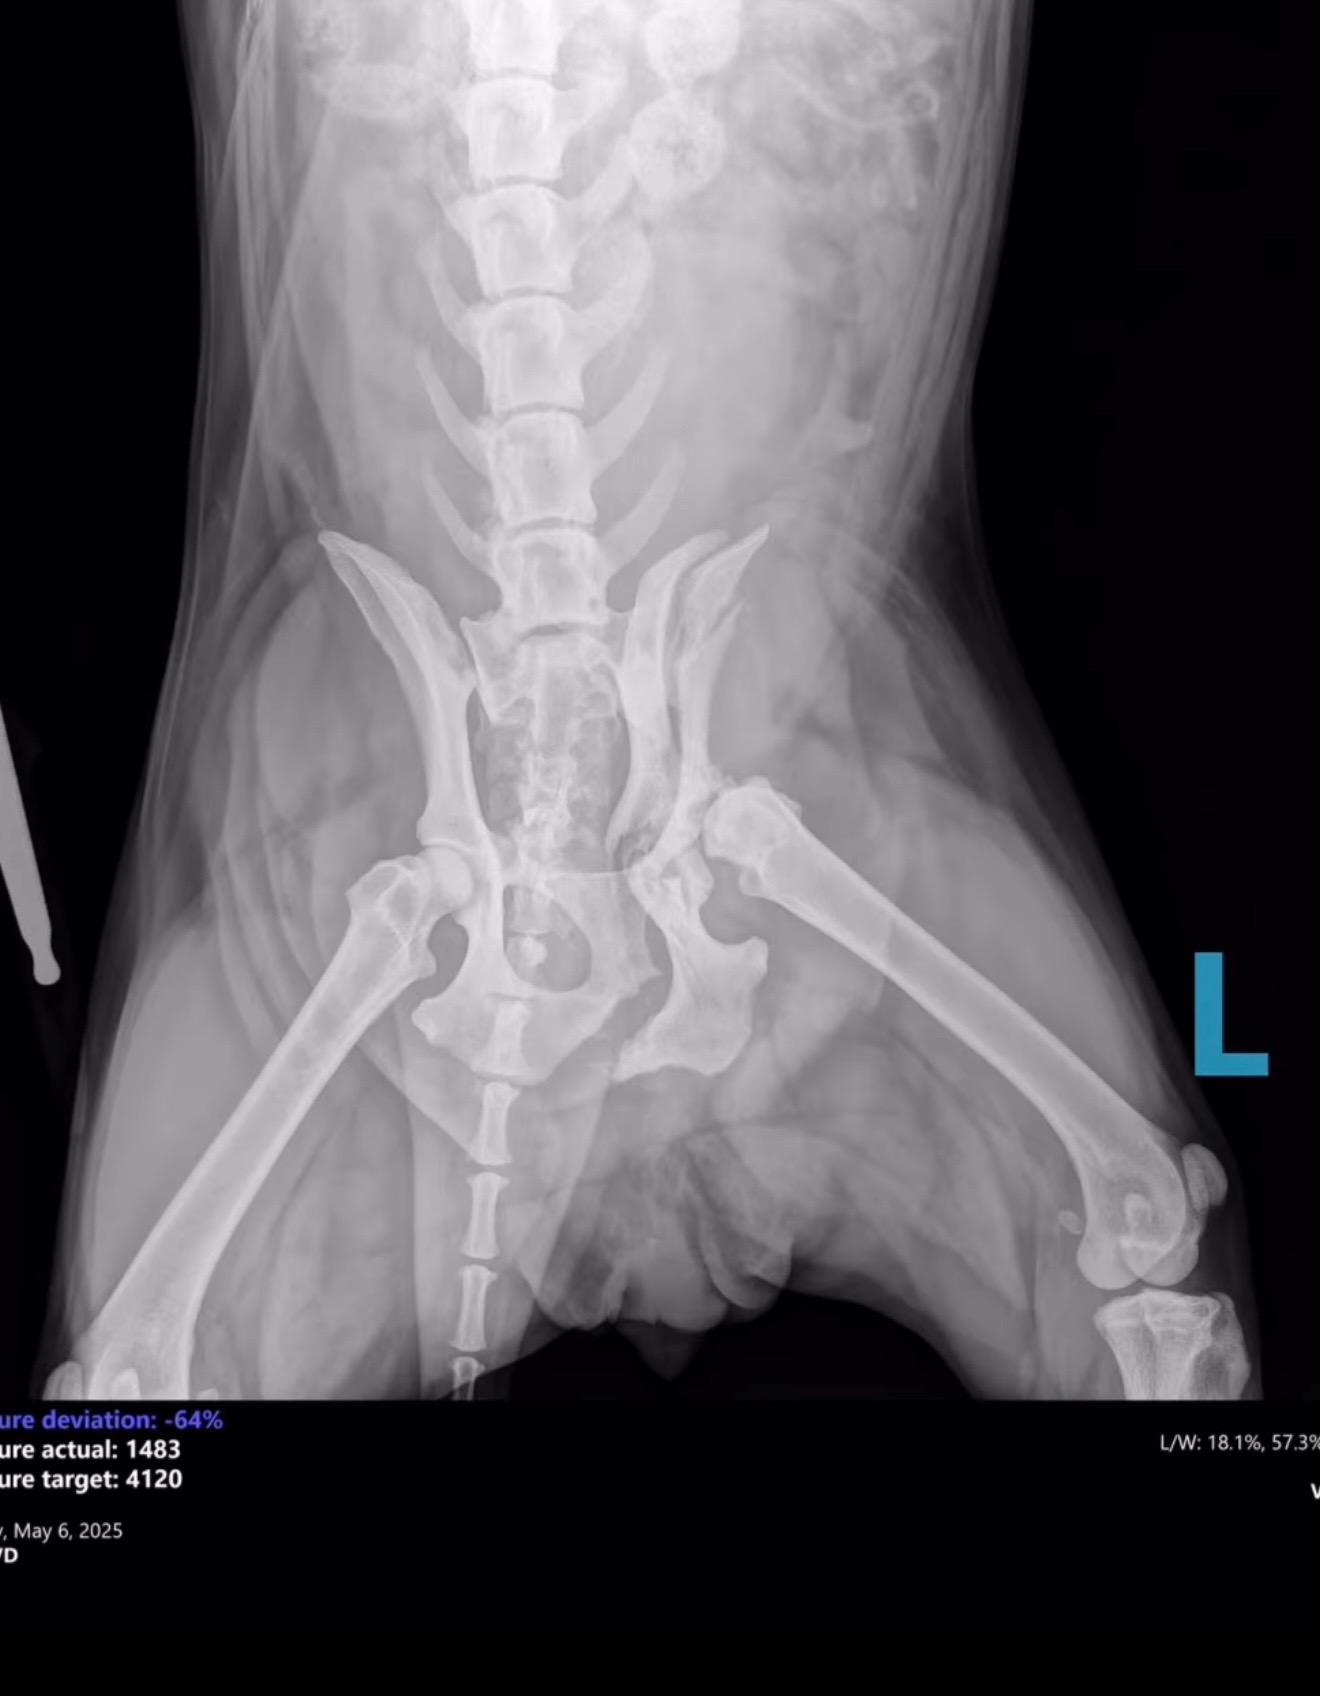

On Monday, a Good Samaritan found Harper in Dekalb County broken and in urgent need of medical attention. Unfortunately, their car broke down on the way to DCAS, and Gwinnett County kindly took her in. Harper arrived without a microchip and the shelter has been unable to locate an owner. We are unsure what caused her injuries exactly, but they are severe.

Harper has suffered multiple fractures on the left side

of her pelvis, including:

1. Left ischium

2. Left acetabulum

3. Crushed left ilial wing

4. Suspected fracture at the left sacroiliac (SI) joint

We’ve attached her kennel X-rays, and a short video to help you get to know her better.